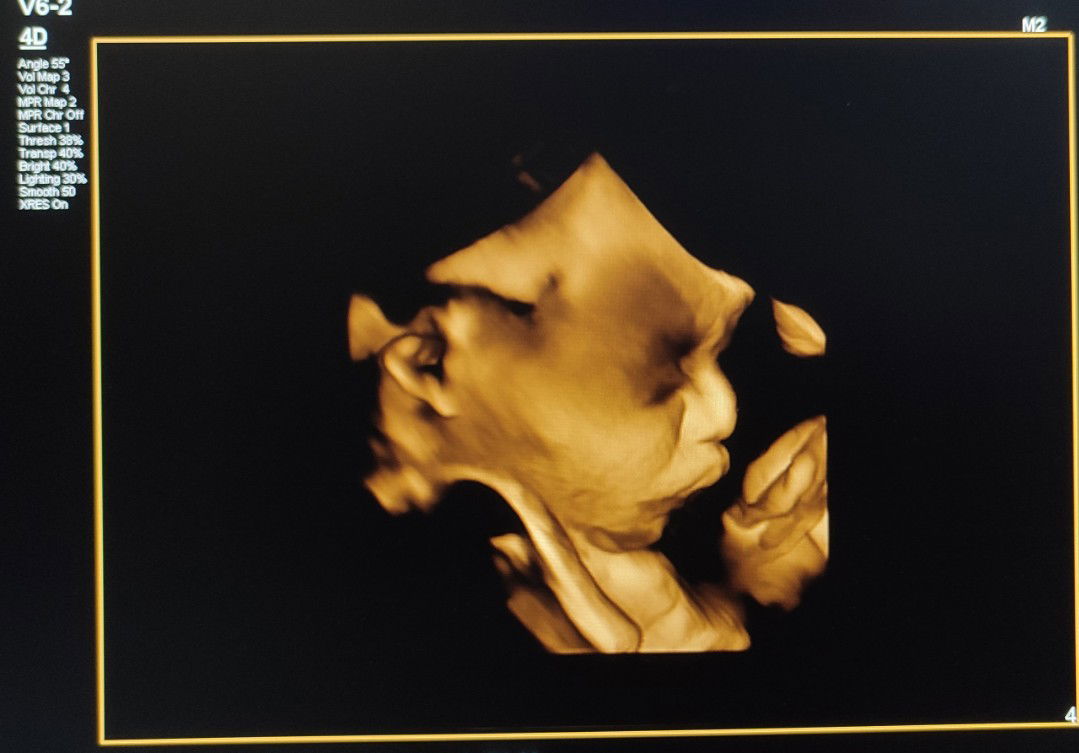

aku riwayat keguguran 2x. skrg hamil ke 3 sudah 31w4d. bedrest. ngerasain kram kontraksi dari awal hamil sampe skrg tm3. entah nanti bisa bedain nggak sama konpal mau lahiran.